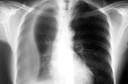

O diagnóstico18 de pneumocistose pode ser dificultado em virtude de que seus sintomas12 são inespecíficos e pela sua concomitância com outras patologias e terapêuticas. A suspeita do diagnóstico18 é feita a partir da história médica do paciente, pela presença dos sintomas12 e pelos achados do exame físico: dispneia14 e sibilos. Os exames complementares mostrarão, na radiografia de tórax19, um infiltrado intersticial20 difuso e perihilar (próximo ao hilo21 pulmonar), lesões22 nodulares, pneumotórax16 e/ou derrame23 pleural. A presença do parasita24 pode ser confirmada no escarro, em lavado brônquico ou em biópsia25 pulmonar. A gasometria arterial e a DHL (desidrogenase lática26) aumentada auxiliam no diagnóstico18.